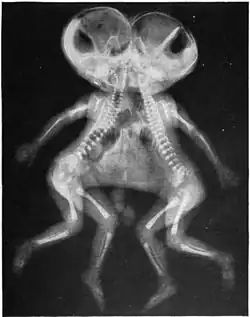

| X-ray of conjoined twins, Cephalothoracopagus. | |

- Cephalothoracopagus: Bodies fused at the head and thorax, with two faces facing in opposite directions, or sometimes with a single face and an enlarged skull.[13][16]